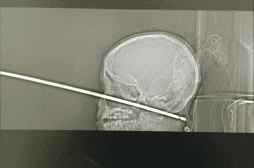

crâne